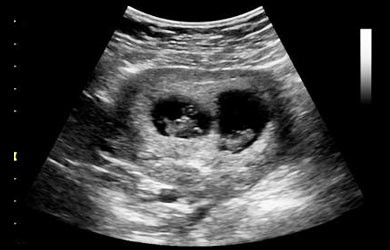

MULTIPLE PREGNANCY

• It is a condition where the woman is carrying more than one baby in the womb. It may be twins, triplets or more.

• It is a very common condition associated with Assisted Reproductive Treatment.g

Types:

• Dizygotic or Non identical Twins:

• Results from the fertilization of two ova.

• Monozygotic or identical twins:

• Results from the fertilization of single ova.